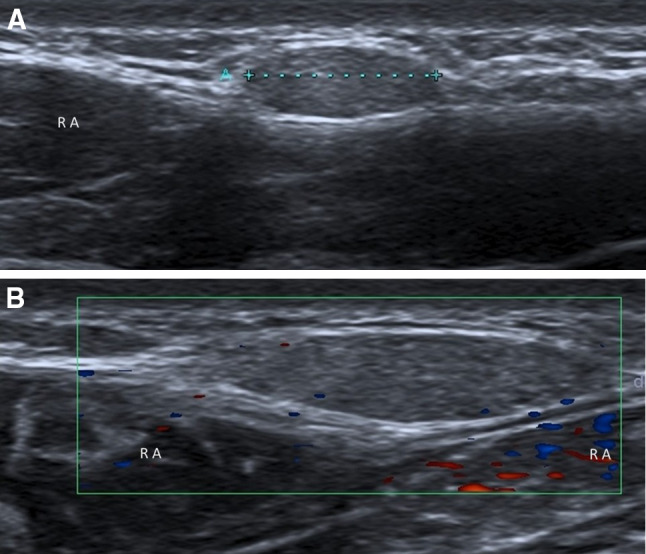

Fig. 8.

Diastasis of the rectus abdominis muscles (a, b). Diastasis of the rectus abdominis muscles is defined as an interrectus distance of 22 mm or more (a calipers), assessed three centimeters above the umbilicus. This measure must be taken in a relaxed state of the patient, avoiding traction that can make muscles to get closer to each other. b Ultrasound panoramic image. RA rectus abdominis, LA linea alba